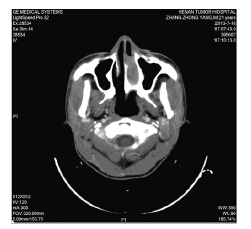

1 病例资料患者,男,22岁,因“左侧鼻塞2月”于2013年7月就诊,无发热、盗汗、体重减轻。血常规、凝血功能、乳酸脱氢酶(LDH)均正常,EBV-DNA 1.05×105/L。CT示:左侧鼻腔内见团块状软密度组织影,左侧下鼻甲部分骨质被破坏,左侧上颌窦内见密度增高影,窦壁骨质结构未见明显异常,左侧上颌窦少许炎症,见图 1。彩超示:双侧颈部、锁骨上下区、腋窝、腹股沟、肝、胆、胰、脾、腹主动脉及下腔静脉旁淋巴结均未见异常。骨髓细胞学检查未见异常。行左侧鼻腔肿物切除术,病理示:(左侧鼻腔)非霍奇金淋巴瘤,免疫组织化学:CD2(+),CD56(+),Granzyme-B(+),CD3(+),CD20(-),Ki-67(+60%),EBER(+),符合结外NK/T细胞淋巴瘤,鼻型,见图 2。诊断:结外NK/T细胞淋巴瘤,鼻型,ⅠA期,IPI评分0分。给予地塞米松+异环磷酰胺+顺铂+依托泊苷+门冬酰胺酶(DICE+L-asp)方案化疗6个疗程。化疗后行PET-CT检查完全缓解,见图 3。6个疗程化疗后第7天出现持续发热,最高39.5℃,无寒战、伴咳嗽、腹胀、腹痛、便血。查体:中度贫血貌,全身皮肤黏膜中度黄染,无皮下出血。口腔黏膜完整,咽充血、水肿、双侧扁桃体无肿大。颈后三角区可触及一2 cm×2 cm肿大淋巴结,质韧、无压痛、固定,余浅表淋巴结未触及肿大。心肺听诊无异常。腹部轻度肿胀,右下腹轻压痛,无反跳痛。肝脏肋缘下3 cm,质中,无压痛。脾肿大,肋缘下3 cm。双下肢轻度水肿。辅助检查:D-二聚体 2.0 mg/L,纤维蛋白原0.26 g/L;血常规: WBC 0.98×109/L,HB 21 g/L,PLT 11×109/L,淋巴细胞 0.56×109/L。肝功能:总胆红素103.7 μmol/L,直接胆红素93.7 μmol/L,间接胆红素10.0 μmol/L,谷丙转氨酶 93 u/L,谷草转氨酶524 u/L,白蛋白27.5 g/L,β2微球蛋白3.78 mg/L。EBV-DNA 3.02×105/L;CMV-DNA(-)。铁蛋白2 000 μg/L。外周血象:淋巴细胞占58%,异型淋巴细胞占34%,见图 4。骨髓象:淋巴细胞占7.5%,其中异型淋巴细胞占3%,见图 5。综合考虑诊断为鼻腔NK/T细胞淋巴瘤合并IM,给予更昔洛韦、阿糖腺苷抗病毒治疗,同时给予抗感染、保肝、输血等对症支持治疗,患者病情好转,症状体征消失,血象与肝功能等实验室检查正常。现已临床随访半年,病情稳定。

| 图 1 鼻腔NK/T细胞淋巴瘤治疗后并发传染性单核细胞增多症患者鼻咽CT影像学表现 Figure 1 Nasopharyngeal CT imaging of patient with nasal NK/T cell lymphoma complicating infectious mononucleosis after chemotherapy |